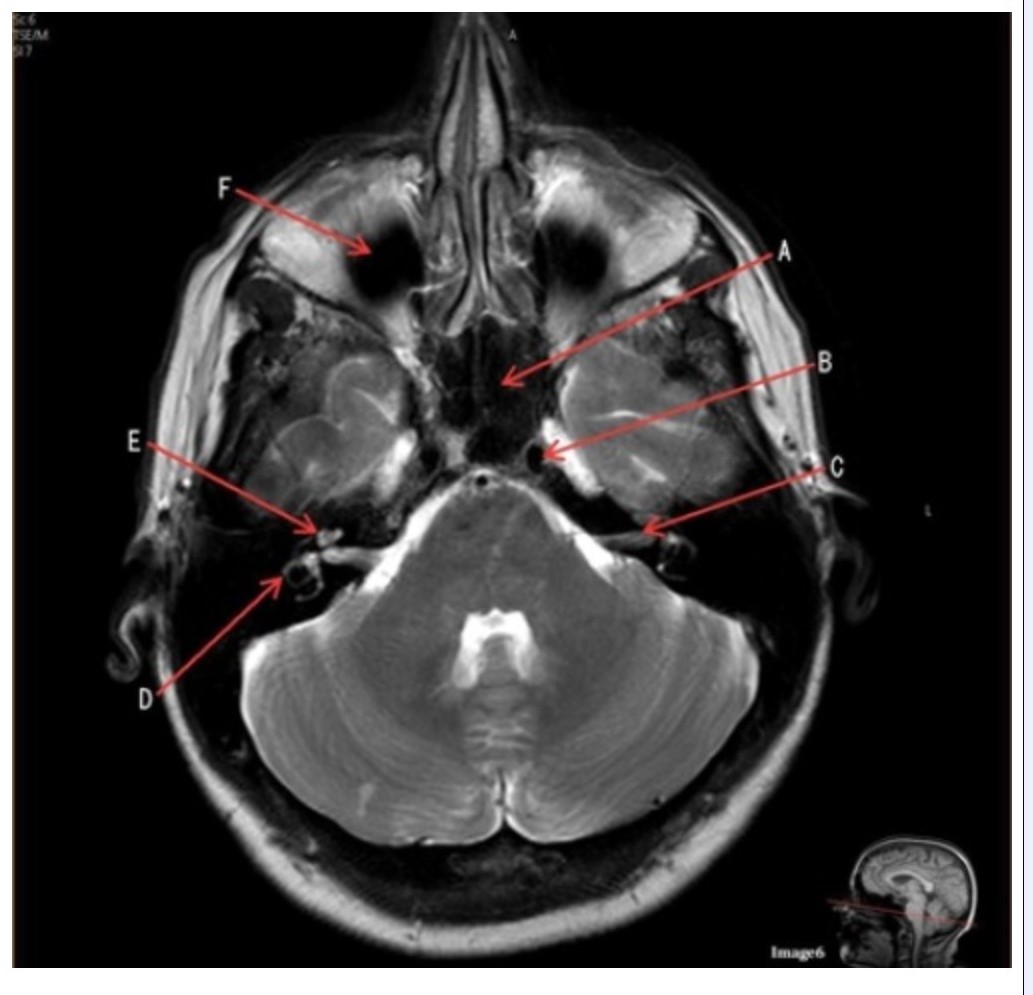

Letter A in Image 6 is pointing to:

A. Maxillary sinus

B. Sphenoid sinus

C. Frontal sinus

D. Internal carotid artery

Letter C in Image 6 is pointing to:

A. 7th cranial nerve

B. Cochlea

C. Trigeminal nerve

D. Semicircular canal

Letter B in Image 6 is pointing to:

A. Maxillary sinus

B. Sphenoid sinus

C. Vertebral artery

D. Internal carotid artery

Letter F in Image 6 is pointing to:

A. Maxillary sinus

B. Sphenoid sinus

C. Frontal sinus

D. Optic chiasm

Image 6 is an example of a _____ weighted sequence acquired in the _______ imaging plane.

A. T1; Axial

B. T1; Coronal

C. T2; Axial

D. T2; Coronal

E. STIR; Axial

Letter E in Image 6 is pointing to:

A. 7th cranial nerve

B. Cochlea

C. Trigeminal nerve

D. Semicircular canal